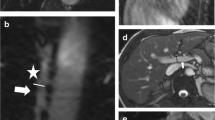

Results are summarised in Table 2 and an examples of a caval subtraction PCMRI and cardiac cine MRI studies are shown in Figs. 2 and 3. Baseline mean PV flow (sham 181.4 ± 12.1 vs BDL 68.5 ± 10.1 ml/min/100 g, p < 0.0001) and TLBF (sham 214.3 ± 16.7 vs BDL 152.3 ± 18.7 ml/min/100 g, p = 0.03) were significantly lower in BDL compared with sham-operated animals. Conversely, HA flow (sham 33.0 ± 11.3 vs BDL 83.3 ± 19.1 ml/min/100 g, p = 0.04) and HA fraction (sham 14.4 ± 4.4 vs BDL 51.5 ± 6.8%, p = 0.0005) were significantly higher in BDL versus sham-operated animals.

Caval subtraction PCMRI data from a sham-operated rat. Magnitude, matched phase-contrast velocity maps with segmented vessels shown as dashed white ROIs and corresponding flow curves through the cardiac cycle for the portal vein (a, b, c), proximal IVC (a, b, d) and distal IVC (e, f, g). In this example, measured PV flow was 29.9 ml/min, caval subtraction TLBF was 41.8 ml/min and HA flow was 11.9 ml/min

An example of a cardiac cine MRI study is shown in Fig. 3. Baseline cardiac systolic function did not differ significantly for heart rate (sham 333 ± 8 vs BDL 341 ± 9 bpm, p = 0.53), but end-diastolic volume (sham 0.66 ± 0.02 vs BDL 0.77 ± 0.03 ml, p = 0.02), stroke volume (sham 0.42 ± 0.02 vs BDL 0.57 ± 0.04 ml, p = 0.006) and cardiac output (sham 140.0 ± 8.0 vs BDL 195.5 ± 15.2 ml/min, p = 0.007) were significantly higher in BDL than sham-operated animals. LV ejection fraction (sham 63.2 ± 2.4 vs BDL 73.7 ± 2.8%, p = 0.01) and cardiac index (sham 291.5 ± 13.3 vs BDL 456.1 ± 33.4 ml/min/kg, p = 0.0009) were also significantly higher in BDL versus sham rats. LV mass did not differ significantly between BDL and sham-operated animals (sham 0.90 ± 0.06 vs BDL 0.98 ± 0.06 g, p = 0.34), but LV mass index was significantly higher in BDL rats (sham 1.87 ± 0.13 vs BDL 2.30 ± 0.13 g/kg, p = 0.03) (Figs. 4, 5, and 6).